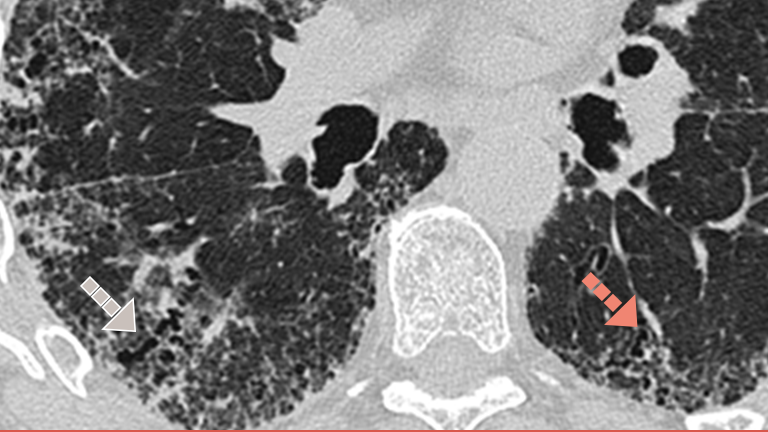

Cum puteți depista și diagnostica PID fibrozantă la debut în cazul pacienților dumneavoastră cu BTC?